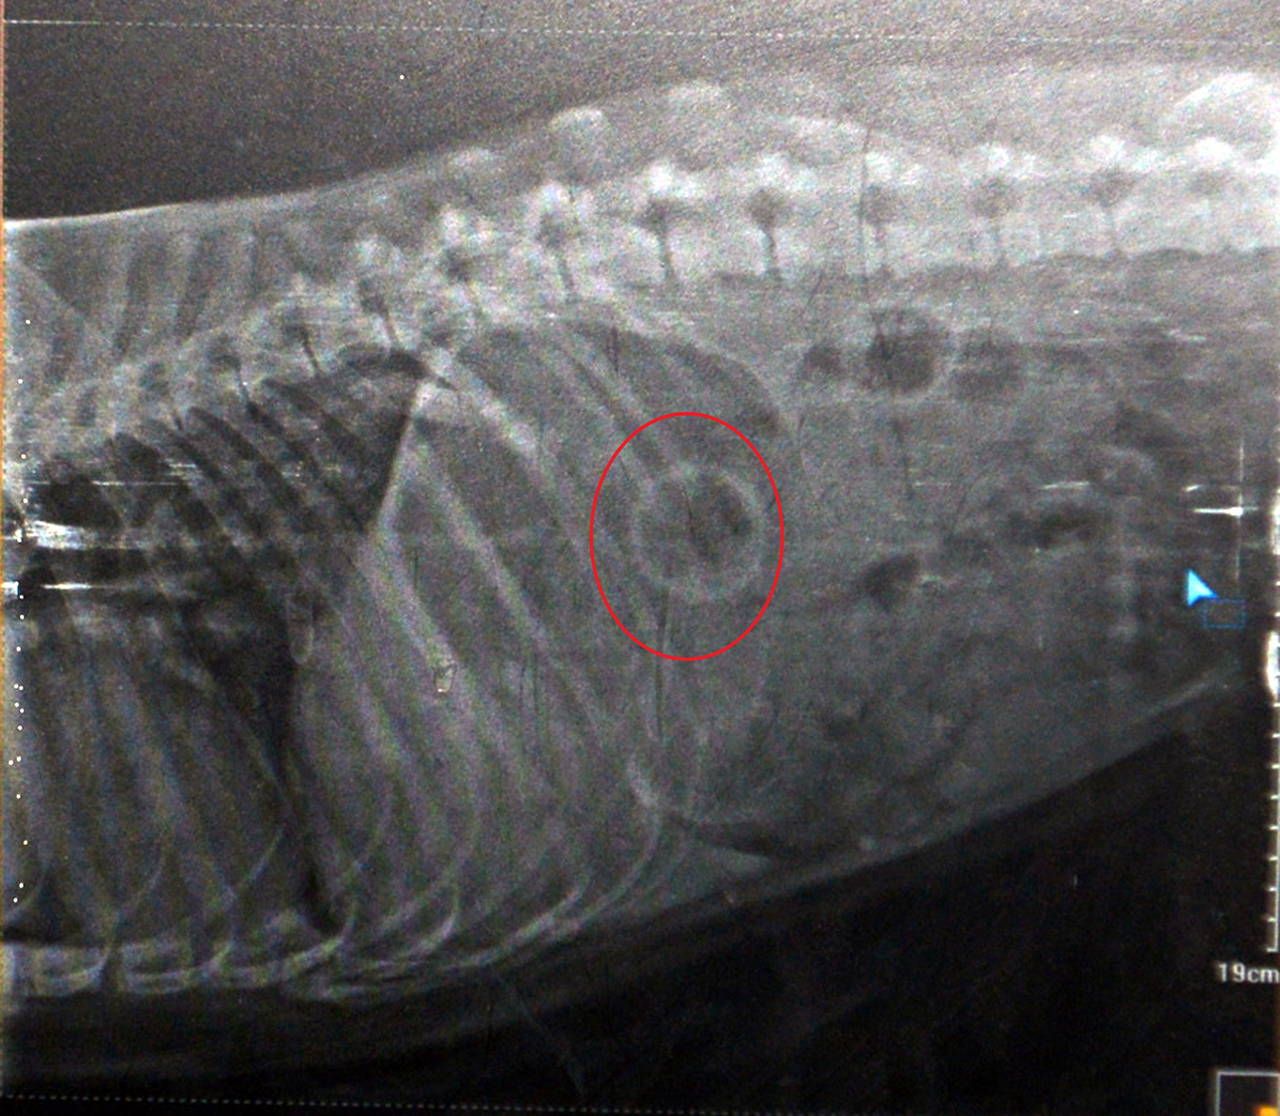

Bozkurt, hemen müdahale ederek topu çıkarmaya çalıştı ama başaramadı. Bir süre köpeğin topu çıkarmasını bekleyen Bozkurt, bu durum gerçekleşmeyince veterinere gitti. Veteriner hekim Mete Betin tarafından mide röntgeni çekilen Bella, topun yerinin tespit edilmesinin ardından ameliyat edildi. Operasyon sonrası Bella’nın midesindeki top çıkarıldı.

Ameliyatı yapan veteriner hekim Mete Betin, zor operasyon olduğunu, 45 dakika sürdüğünü ve sonucun başarılı olduğunu söyledi. Bella’nın midesindeki topu cerrahi müdahaleyle çıkardığını kaydeden Betin, “Sağlığı iyi durumda. Tabii bir süre sıvı beslenmesi gerekiyor. Sonra normal hayatına dönecek. Bu tür durumlarda yutulan cisim bağırsakları tıkarsa ölüme neden olabilir. Evcil hayvan sahiplerinin dikkatli olması lazım. Hızlı müdahale çok önemli. Hayvanların yutamayacakları büyük toplarla vakit geçirmelerine izin verilmelidir. Yutabilecekleri cisimleri onlardan uzak tutmalıyız” diye konuştu.